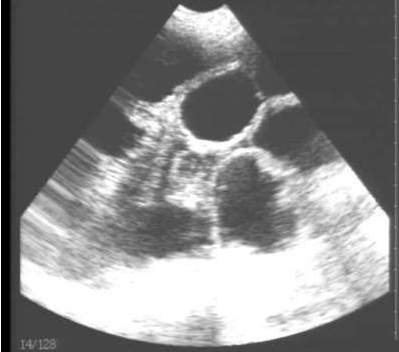

獸用B超機檢測母豬有胎兒圖像

豬用B超機檢測有胎兒圖像